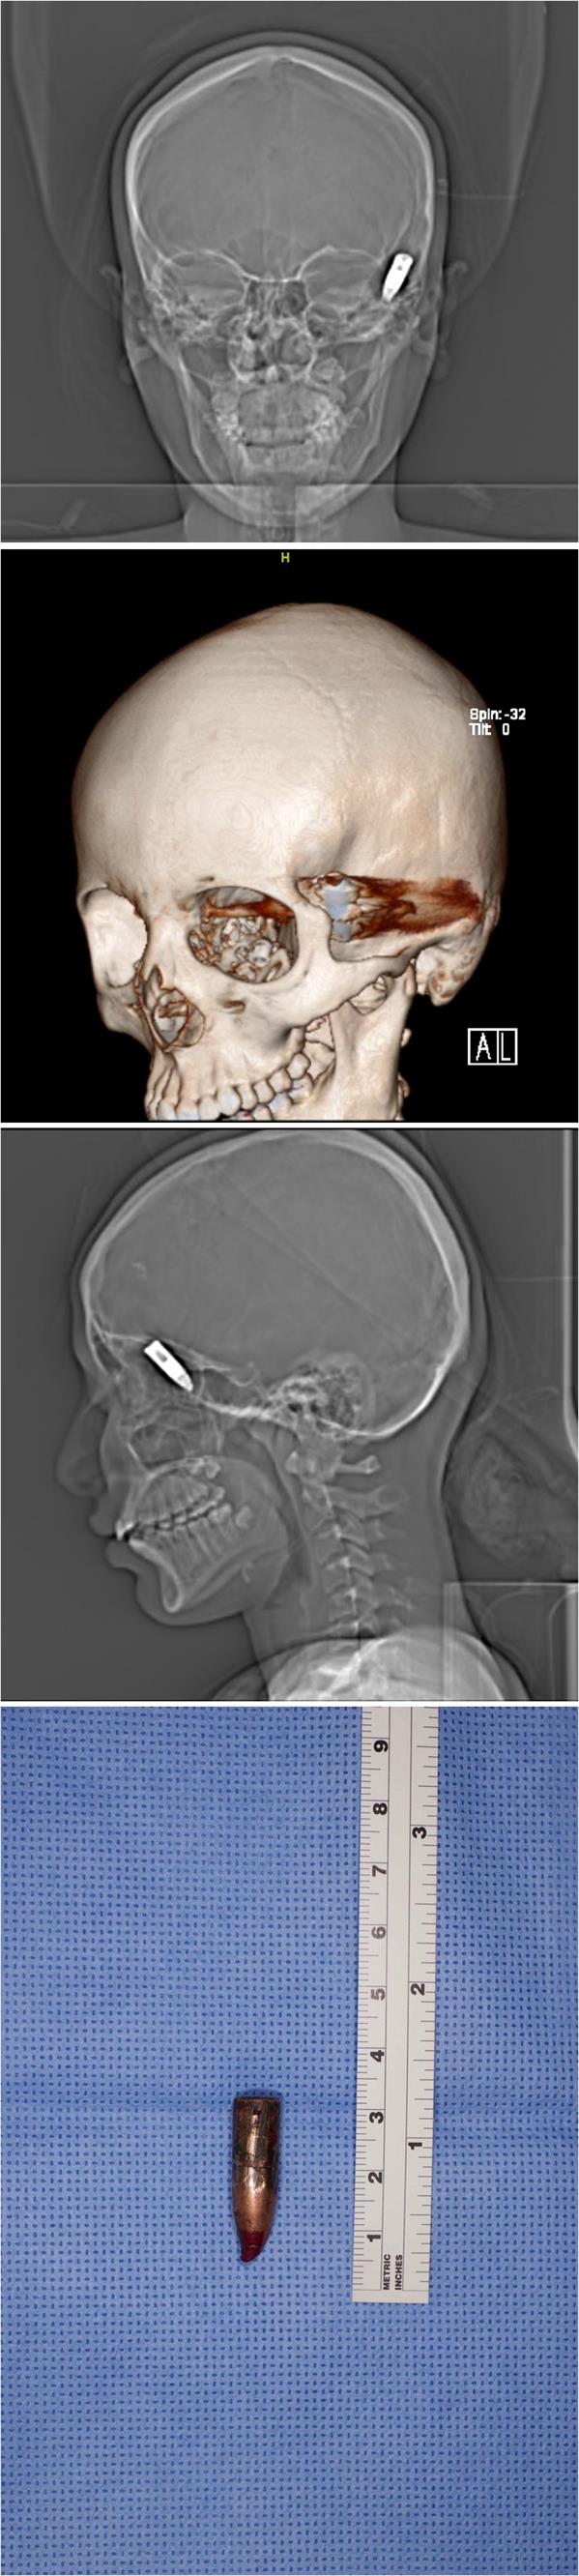

تمكّن فريق طبي بمدينة الملك فهد الطبية من إنقاذ حياة فتاة تعرّضت لإصابة بعيار ناري انطلق من إحدى مناسبات الأعراس بوادي الدواسر.

وكانت الفتاة برفقة والديها في إحدى الاستراحات المجاورة لموقع المناسبة، حيث أصابها العيار الناري واستقر في رأسها، ما استدعى نقلها على وجه السرعة للمستشفى.

وقالت مدينة الملك فهد الطبية إن الفريق التابع لقسم جراحة الوجه والفكين نجح في استخراج الطلقة من رأس الفتاة، وإنها الآن في وضع مستقر.